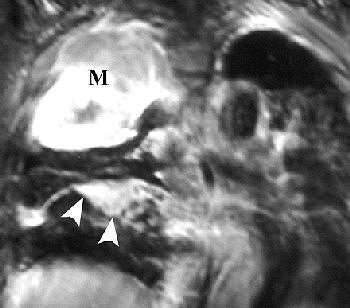

![]() |

R imaging evaluation of MPM in 63-year-old man. Coronal (top) and contrast-enhanced fat-saturated (below) T1-weighted MR images show a large, enhancing right apical mass with invasion of chest wall (black arrows, top). An enhancing right major fissure is also seen (white arrowheads, below). Figure 16, Wang ZJ, Reddy GP, et al, "Malignant Pleural Mesothelioma: Evaluation with CT, MR Imaging, and PET" (RadioGraphics 2004; 24: 105-119).

Investigators from the University of California, San Francisco came to similar conclusions, advocating MR imaging in patients with potentially resectable disease.

"The excellent contrast resolution of MR imaging can allow improved detection of tumor extension.... Loss of fat planes, extension into mediastinal fat, and tumoral encasement of more than 50% ... are some of the features that suggest tumor extension," wrote Dr. Zhen Wang and colleagues in an educational exhibit for RadioGraphics (January-February 2004, Vol. 24:1, pp. 105-119).

On T1-weighted MR images, malignant pleural mesothelioma (MPM) is typically isointense or hyperintense. On T2-weighted images, MPM is moderately hyperintense. In both cases, gadolinium enhances the disease, they added.

MRI may also prove superior for assessing the growth of MPM, either as an invasion of the diaphragm, invasion of the endothoracic fascia, or a single chest wall focus.